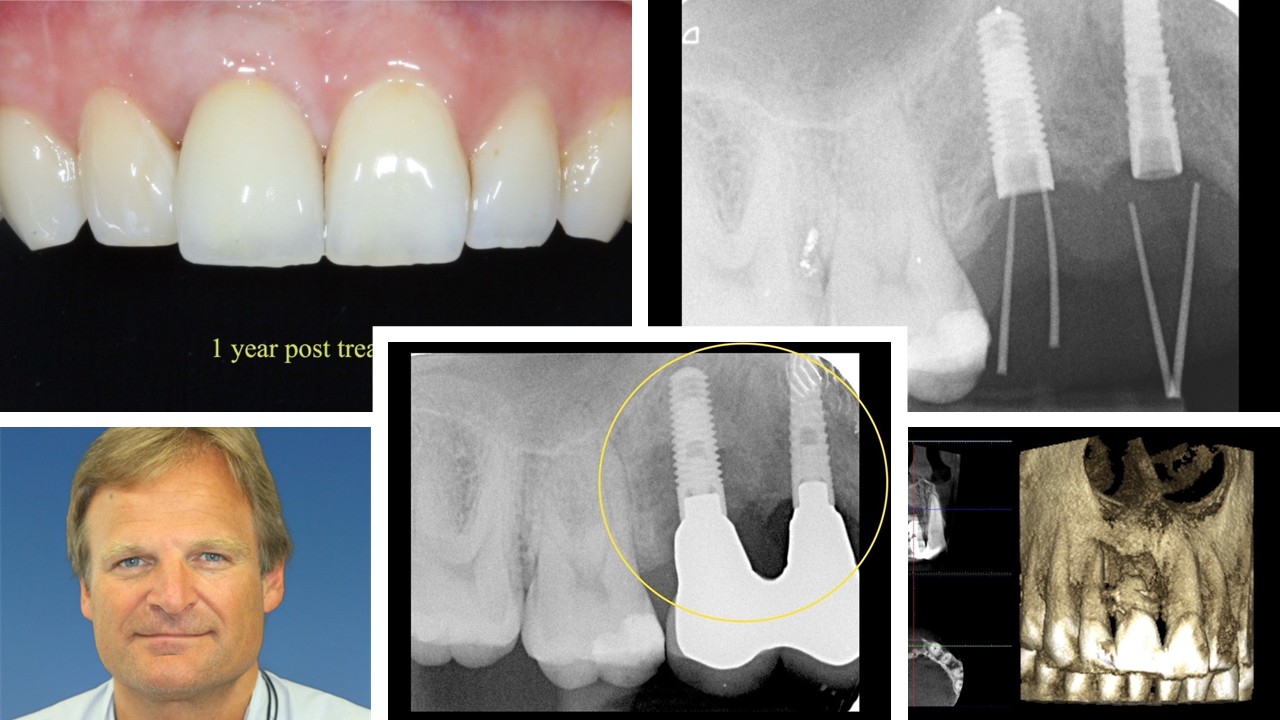

Speaker: Dr. Roy SAMUELSSON

Complications in combination with different treatment procedures, both in the short and long perspectives, will often have consequences and, among other things, usually lead to poor aesthetics. To develop our service to patients, safer protocols with less risk will enhance the results, also in the long term. This will undoubtedly also be good for business. In this webinar, I will show you some suggestions that might come in handy.